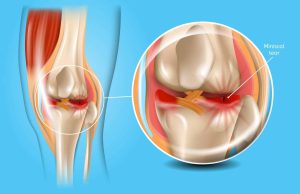

پارگی مینیسک زانو یک آسیب شایع زانو است که میتواند هنگام چرخش ناگهانی زانو، اغلب در حین ورزش یا سایر فعالیت های بدنی رخ دهد. منیسک قطعه ای از غضروف است که بین استخوان ران و استخوان ساق پا محافظت می کند.

علائم پارگی منیسک می تواند شامل درد، تورم، سفتی و مشکل در حرکت زانو باشد. گزینه های درمانی برای پارگی منیسک به شدت آسیب بستگی دارد، اما می تواند شامل استراحت، یخ، فشرده سازی و بالا بردن (RICE)، فیزیوتراپی و در برخی موارد جراحی باشد.